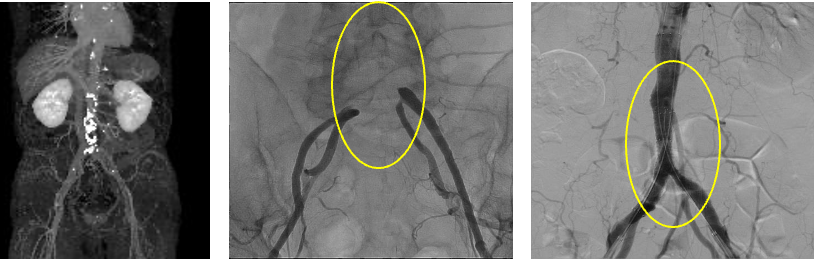

そのほか、③のように腹部大動脈終末部の閉塞に対しての治療なども連携施設と協力して治療を行っています。

③腹部大動脈終末部〜左右総腸骨動脈の閉塞